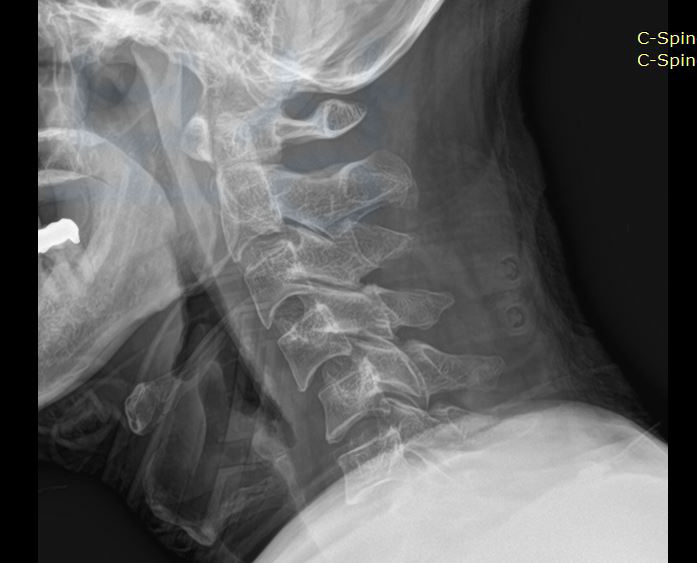

위 진단서를 보시면

경추 7번 압박골절

경추 2번, 4번, 5번 골절

등등의 진단받은 기록입니다. 보존적 치료로 호전을 기대했지만 의뢰인은 경추 4번 5번의 전방 유합술 받으셔야 했습니다. 위 상황으로 의뢰인은 단순히 운동 장해로 만 평가를 받아 후유장해 보험금을 청구하시려고 하셨습니다.

AMA 평가 기준 상 경추 7번 압박골절 대해서는

약간의 기형 15% 지급률

또 경추 4번. 5번의 유합에 대해서는 약간의 운동 장해에 해당하였죠. 한 부위에 둘 중 높은 지급률로 보험금을 청구할 수 있습니다! 보상 파트너는 손해 사정서 및 증빙자료를 함께 준비하여 도와드렸지만 역시나 보험사에서도 조사관을 배정하여 현장조사 및 의료자문을 시행하였습니다.